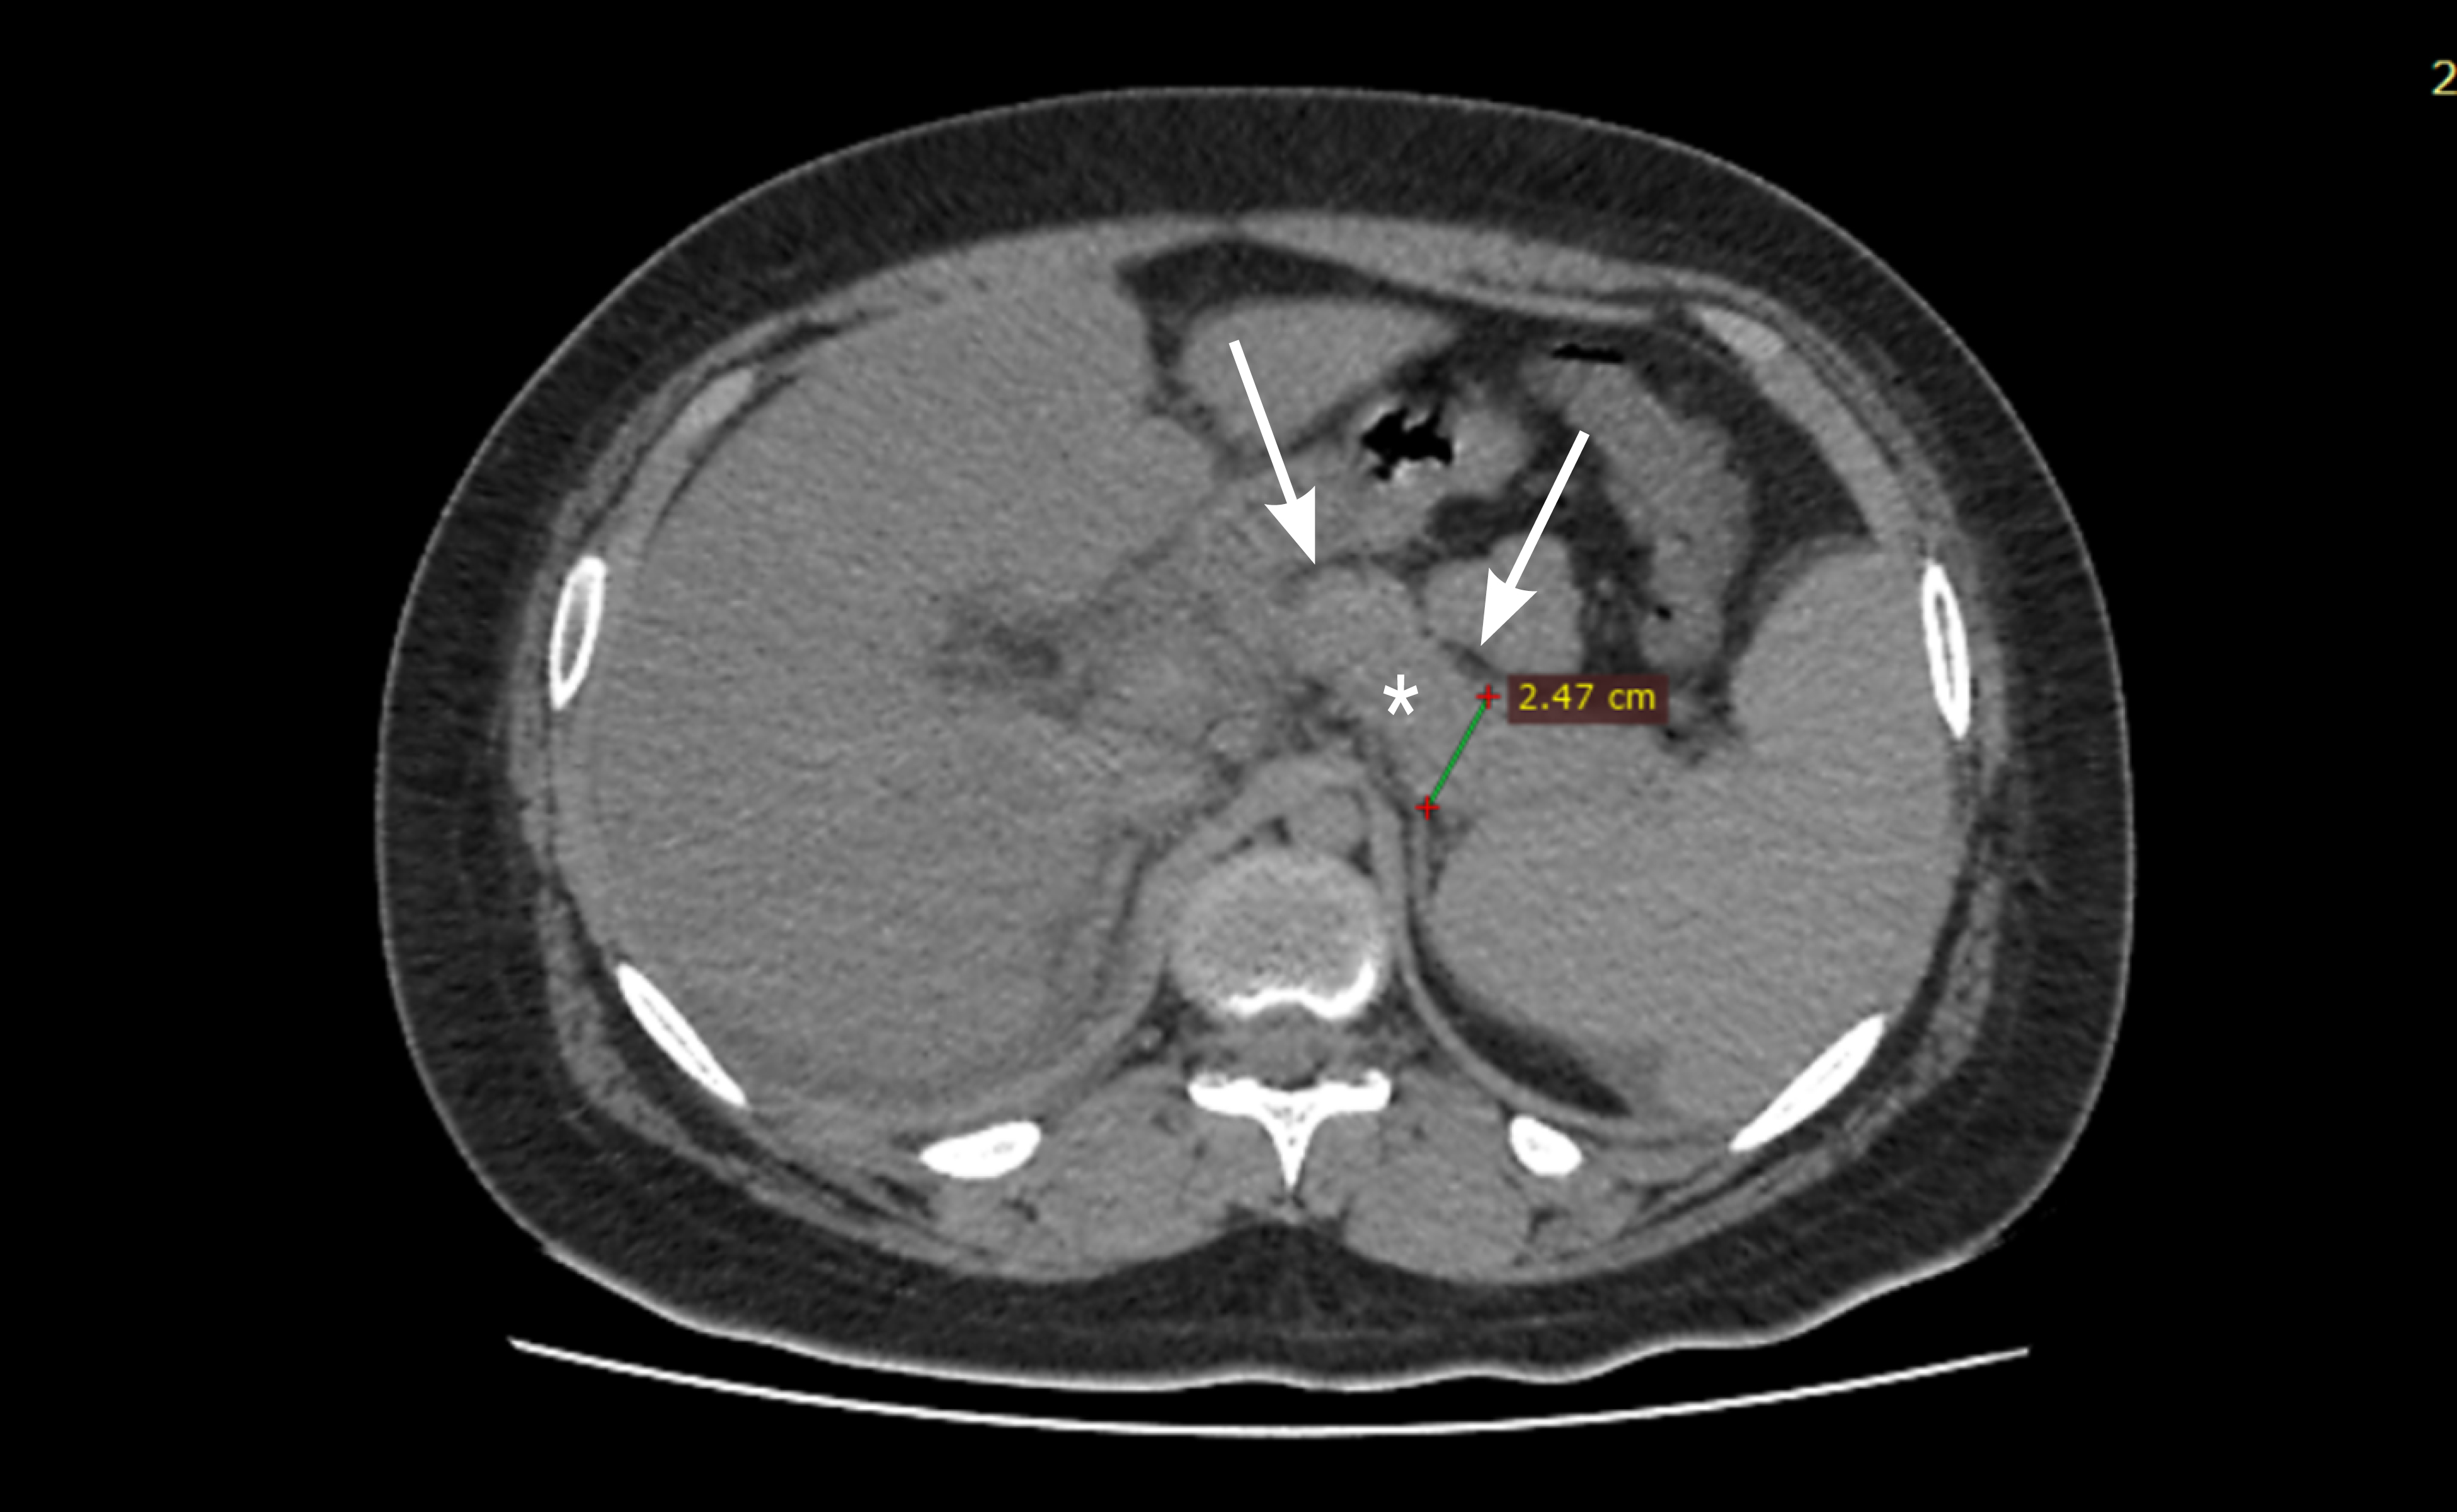

Figure 1